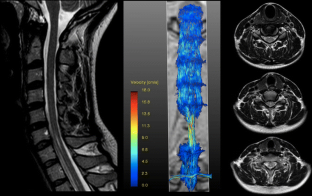

Movie 2

Patient 1 with pronounced Chiari I malformation and presyrinx at the level of C2 showing two flow vortices located bilaterally in the anterolateral subarachnoid space extending from the foramen magnum to the level of C2/C3. (MPG 8426 kb)

4D flow imaging showing severe flow acceleration in patient 2 with two flow jets located bilaterally in the anterolateral subarachnoid space extending from the foramen magnum to the level of C2/C3 with accentuation on the right side (MPG 6200 kb)